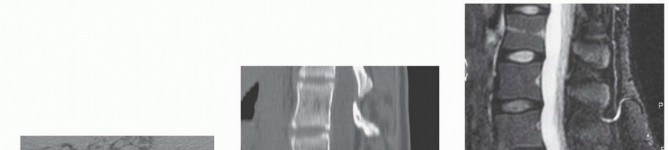

Initial imaging includes standing posteroanterior and lateral radiographs of the spine ( FIG 3A,B ). Oblique views ( FIG 3C )

may provide additional information in certain cases, but their use for diagnosing spondylolysis without listhesis in adolescents is controversial.1

FIG 3 • Posteroanterior (PA) (A), lateral (B), and oblique (C) radiographs demonstrating high-grade spondylolisthesis.

(continued)

FIG 3

•

Axial (

D

) and sagittal (

E

) CT scan sections demonstrating bony deformity.

F.

MRI demonstrating high-grade spondylolisthesis.

Plain radiographs are used to establish the overall alignment of the spine in both the coronal and sagittal plane. The sagittal alignment should be noted, particularly the degree of lumbar lordosis above the lumbosacral kyphosis. Any structural abnormalities in the spine in addition to the slip should be noted. These abnormalities

include the presence of spina bifida occulta, scoliosis, or sagittal plane abnormalities. Other spinal problems should be treated as per individual merits.

Coned down view of lumbosacral junction and Ferguson view (20-degree cranially angulated AP x-ray centered over lumbosacral junction) may also be performed to rule out coexistent far out syndrome.

Computed tomography (CT) scans with three dimensional (3-D) reconstruction are valuable in defining the exact bony abnormality and will help in preoperative planning (

FIG 3D,E

).

Magnetic resonance imaging (MRI) studies are indicated when there is evidence of neurologic compromise. MRI provides good visualization of nerve roots, spinal stenosis, and cauda equina compression (

FIG 3F

*).